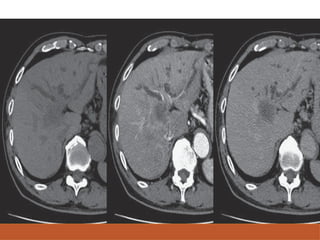

CT SCAN NECT: largehypodense mass, often with central area of low attenuation(necrosis). May be isodense to liver. CECT: non necrotic area enhances strongly in arterial phase & early washout in subsequent phases. Detection of venous invasion (portal,hepatic veins,IVC).

• #31 Axial cect images of hcc in segment 4a in showing enhancement odf elsion in arterial phase and washout of tumour in portal venous phase and delayed phases So early washout of the contrast suggestive of hcc